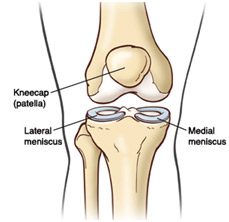

The knee is comprised of the femur (upper thigh bone) and tibia (lower leg bone) and fibula (lower leg bone, lateral side). These bones are end-capped by cartilage, which acts as a protective barrier between the bones (as we age, these layers degenerate, which is when we begin to experience osteoarthritis and DJD). These massive bones are connected by four large ligaments the Anterior, Lateral, Medial and Poster cruciate ligaments. To prevent grinding between these bones we have the medial meniscus and lateral meniscus, two c-shaped shock absorbers comprised of cartilage.

The function of the menisci aid in transmission of the load of the body, aid in stability, shock absorption and provide nutrition and lubrication to the articular cartilage – the tissue that is the ‘end cap’ to our bones.

The medial meniscus (inside of our knee) is connected to the medial cruciate ligament. Due to these attachment configurations, it is less mobile than the lateral meniscus (outside of our knee) and is more susceptible to potential injury, roughly 55 – 60% of the time. ACL tears, when they occur affect and tear the lateral meniscus owing to their structural proximity.